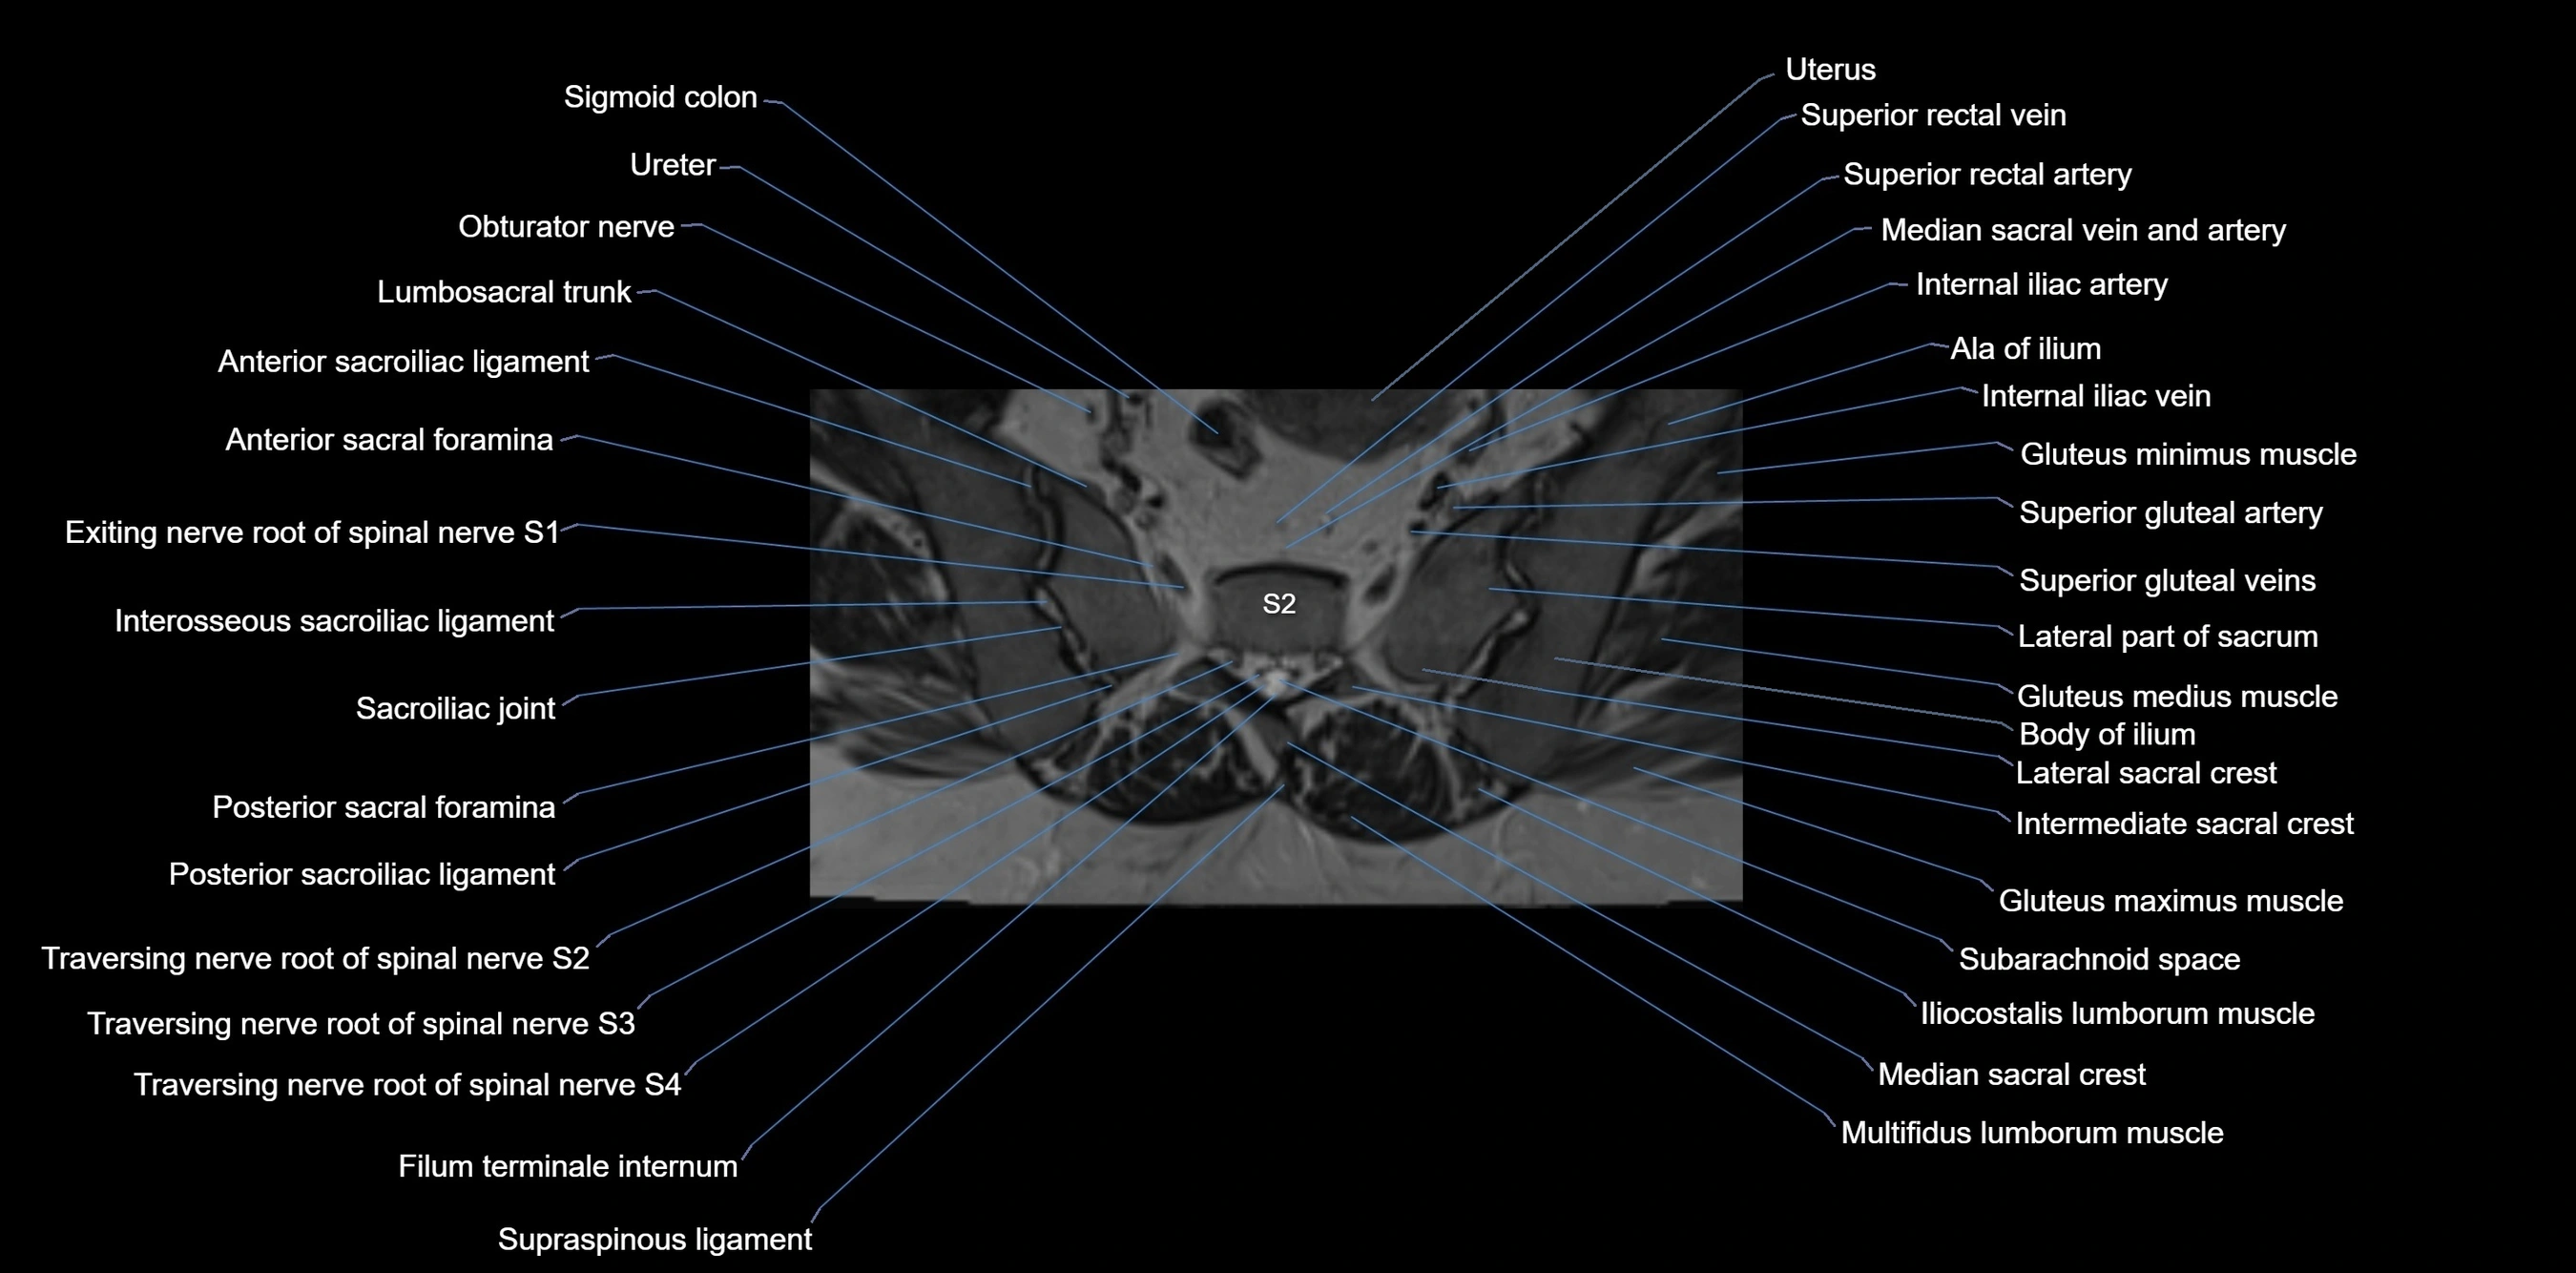

MRI image

image